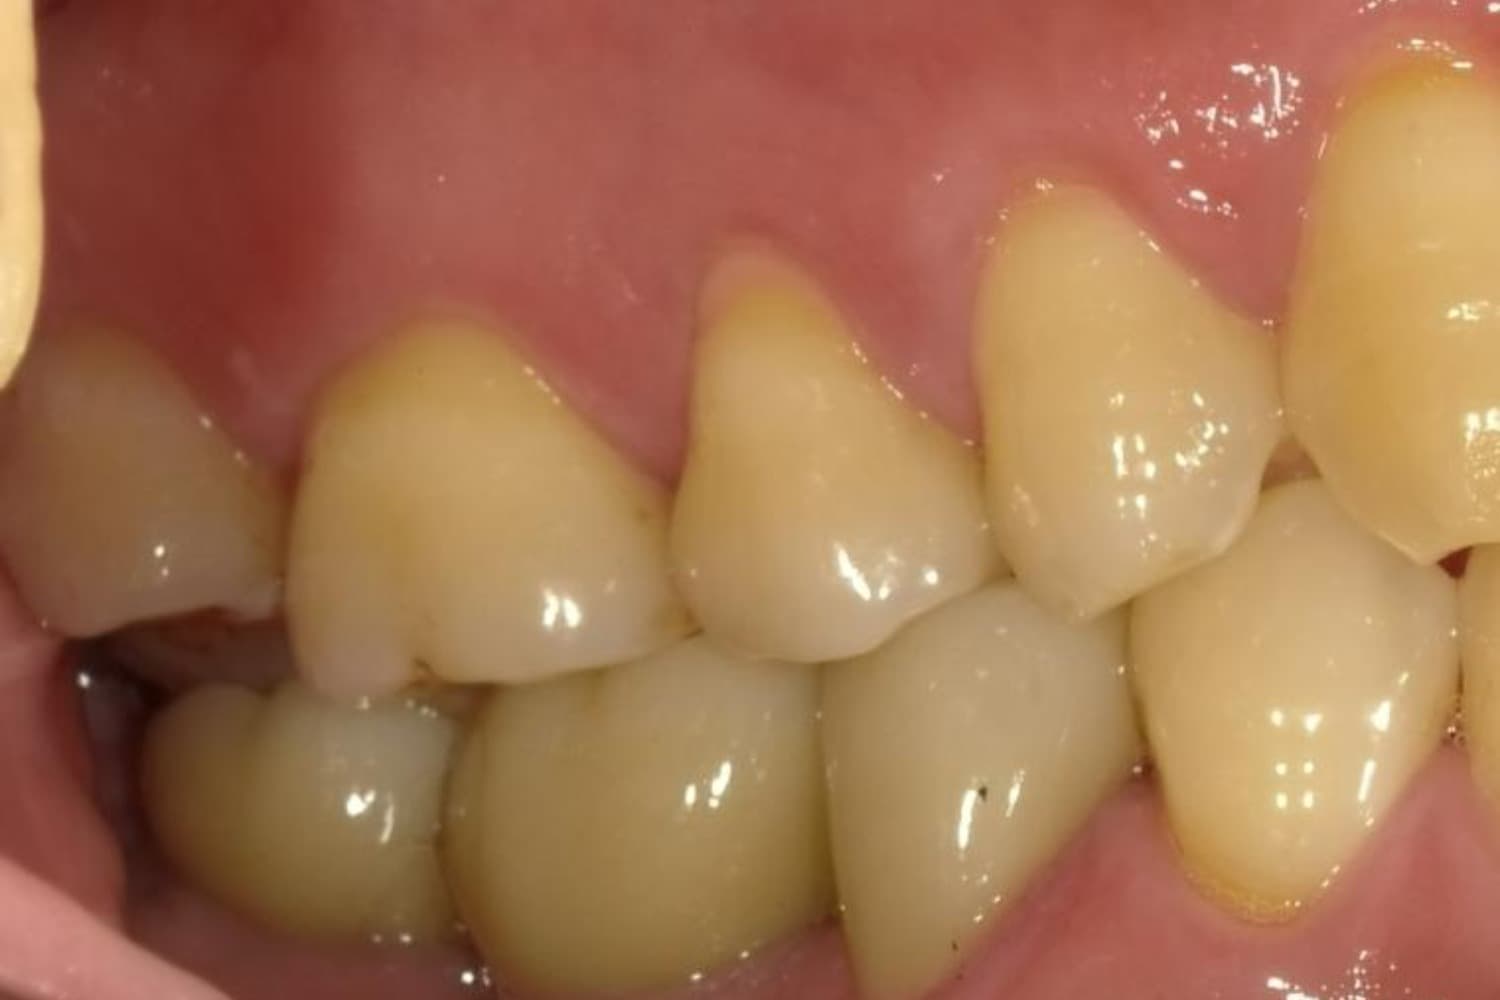

下顎大臼歯3本欠損症例

Before

After

左下第一大臼歯は保存が困難な状態であったため抜歯をおこないました。あわせて、ご来院時から欠損していた右下第一・第二大臼歯も含め、欠損部の補綴方法についてご説明し、インプラント治療を選択されました。

主訴

左下の第一大臼歯は別の医院で治療中でしたが、治療が思うように進まず、加えて他の箇所にも痛みが続いたことから、当院にご相談いただきました。

治療期間

10ヵ月

費用

140万円

副作用・リスク

インプラント治療は外科的な処置を伴い、多少の腫れや痛みが出ることがあります。 多くの場合は鎮痛薬で和らげることができます。